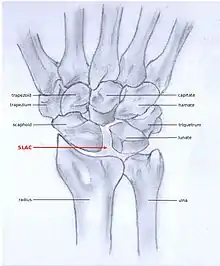

SLAC and SNAC are two patterns of wrist osteoarthritis, following predictable patterns depending on the type of underlying injury. SLAC is caused by scapholunate ligament rupture, and SNAC is caused by a scaphoid fracture which does not heal non-union.

SLAC is more common than SNAC; 55% of the patients with wrist osteoarthritis have a SLAC wrist.[3]

SLAC

Scapholunate advanced collapse (SLAC) is a predictable pattern of wrist osteoarthritis that results from untreated long-standing scapholunate ligament rupture and the associated carpal malalignment.[4] The misalignment is described as dorsal intercalated segment instability (DISI) which is where the lunate angulates towards the dorsal side of the hand.[2][5]